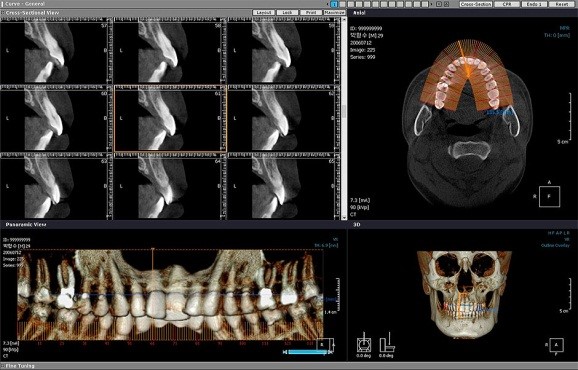

Также в своём распоряжении имеем компьютерный томограф от компании Vatech 3D - производителя наиболее современной и точной диагностической техники в стоматологии. Данный томограф позволяет создать полное 3D изображение челюстно-лицевой области.

Полученное изображение позволяет врачу не только увидеть развитие патологических процессов во всех плоскостях, но и правильно спланировать восстановление зубочелюстной системы пациента, что крайне важно при имплантации зубов, исправления прикуса и многих других стоматологических манипуляциях.